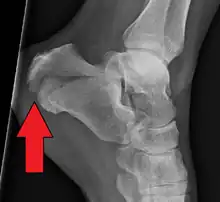

X-ray of a fractured calcaneus

Bohler's angle[14]

The Angle of Gissane, or "Critical Angle", is the angle formed by the downward and upward slopes of the calcaneal superior surface. On a lateral radiograph, an angle of Gissane > 130° suggests fracture of the posterior subtalar joint surface. Böhler's angle, or the "Tuber Angle", is another normal anatomic landmark seen in lateral radiographs. It is formed by the intersection of 1) a line from the highest point of the posterior articular facet to the highest point of the posterior tuberosity, and 2) a line from the former to the highest point on the anterior articular facet. Böhler's angle is normally 25° to 40°.[14] It is named after Austrian physician Lorenz Böhler.[16] A decreased angle is indicative of a calcaneal fracture.